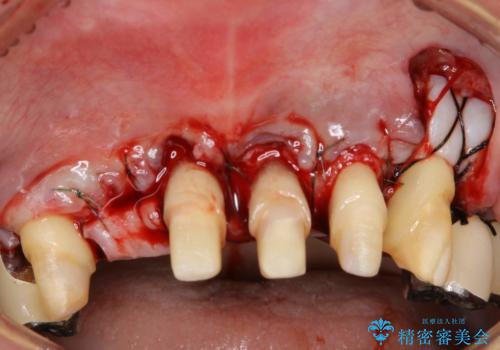

- 歯周病により欠損が生じた歯槽骨、まずは再生治療をおこなう

→治癒後、確定外科を行い完全に歯周ポケットを除去し、最終的に歯周補綴をおこなう